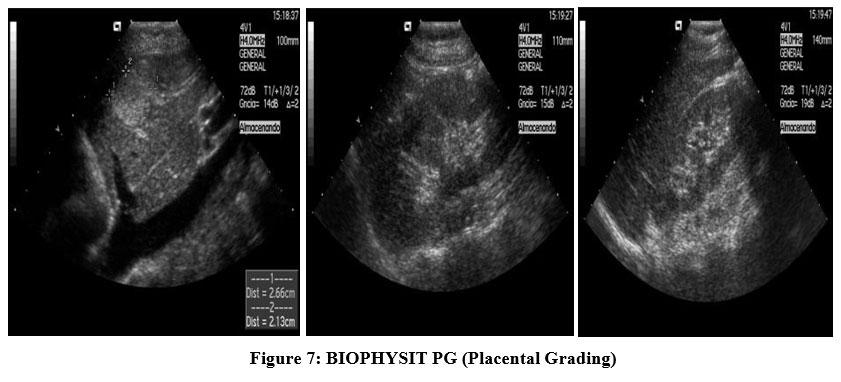

Which of the following are components of the biophysical profile (BPP)? Select all that apply

Explanation

Biophysical profile is a prenatal assessment tool that evaluates fetal well-being using real-time ultrasound and a non-stress test. It measures acute and chronic markers of hypoxia. Components scored include fetal breathing movements, body/limb movements, tone, amniotic fluid volume, and non-stress test. A normal score is 8–10. Normal amniotic fluid index (AFI) is 8–24 cm; normal single deepest pocket is 2–8 cm.

Rationale for correct answers

4. Amniotic fluid volume reflects chronic uteroplacental function. A single vertical pocket ≥2 cm or AFI ≥5 cm is normal.